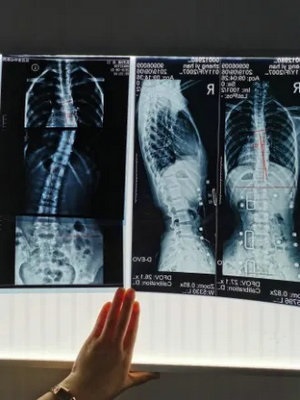

脊柱侧弯是指脊柱在冠状面、矢状面、水平面发生的三维骨骼畸形。X线诊断Cobb角超过10°,即可诊断为脊柱侧弯。患者会出现双肩不等高、腰或背部一侧隆起、对侧凹陷、胸廓畸形等外观改变,并会导致严重的身心健康问题。目前,脊柱侧弯已成为继肥胖症、近视之后我国儿童青少年健康的第三大“杀手”,防控形势严峻,主要表现在:

1.脊柱侧弯筛查需站立位全脊柱X光片正侧位。

2.骨盆前倾:矢状面 Cobb 角>50°。